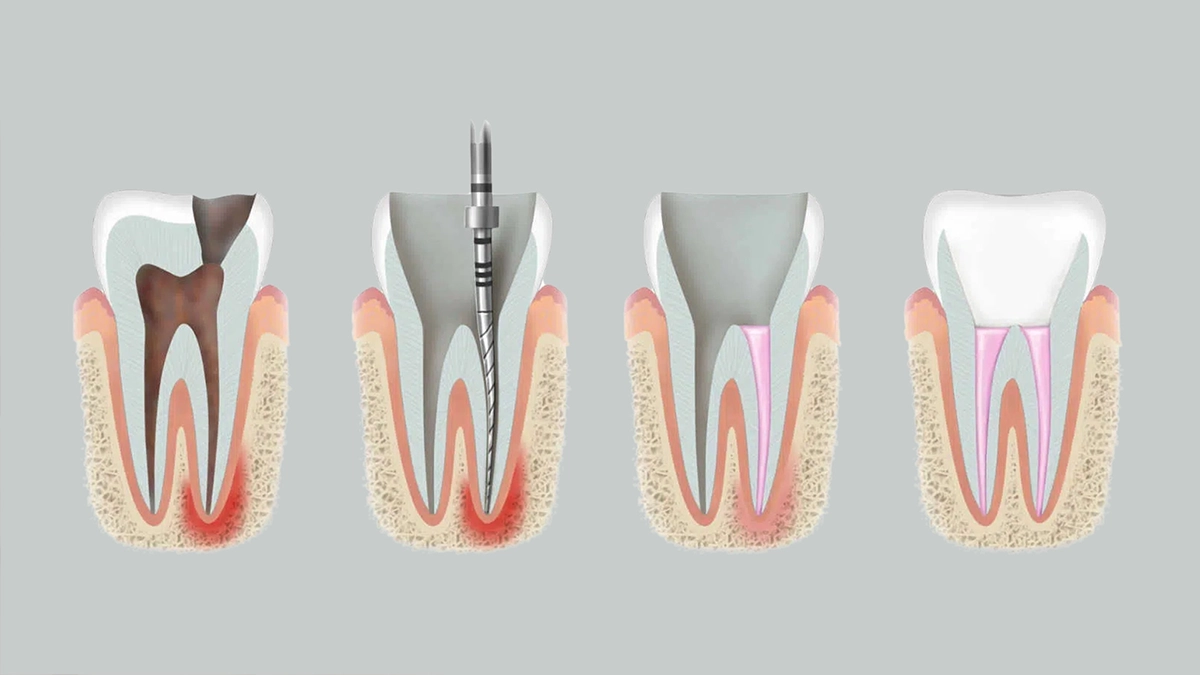

Ağrısız Gülümsemeler İçin: Kök Kanal Tedavisiyle Sağlam Adımlar!